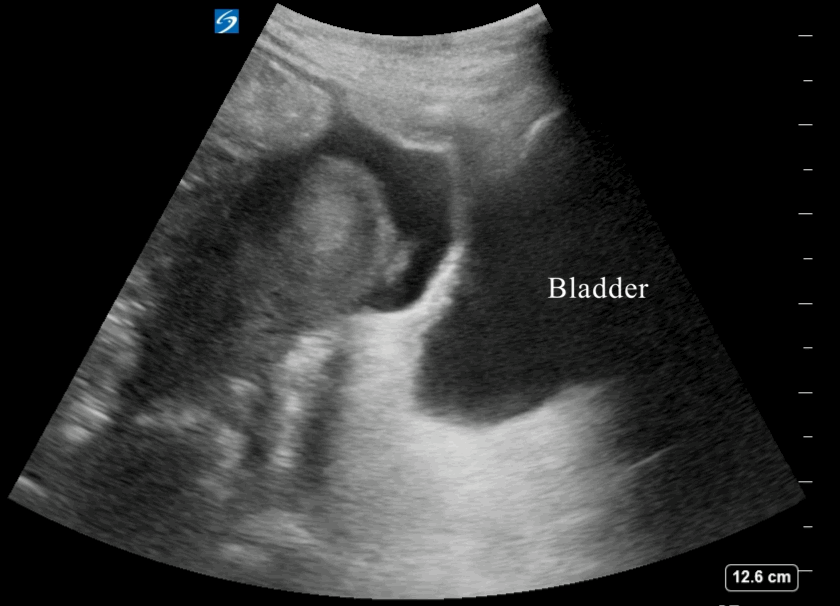

Longitudinal view with full bladder and free fluid in the peritoneum: This longitudinal view shows a full bladder in a male patient. Free fluid is visible above the bladder, within the peritoneum, appearing as black anechoic fluid between the intestines. The presence of free fluid in the peritoneum is clearly identifiable due to the bladder’s distension, allowing better visualization of the fluid above it.